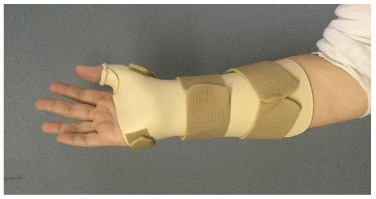

Some fractures require immobilization in a cast or customized splint for eight weeks up to six months. The cast will include the wrist and thumb and may also include the elbow. The fingers will be free to move.

Our senior hand therapists may fabricate a custom orthosis to immobilize the wrist and thumb to protect the healing bone.

Example of an orthosis to protect the healing bone after a scaphoid fracture